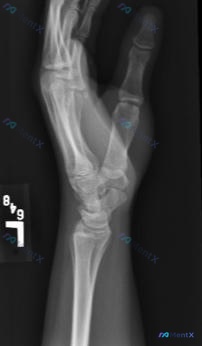

整理了一个很有启发性的运动损伤病例,核心在于「不要被正常的静态X光片带偏」。 --- 病例资料 - 患者:22岁女性体操运动员 - 病史:左手腕疼痛不适1个月,有韧带病史,已接受手腕保守治疗 - 影像(X光正侧位): - 桡骨远端、尺骨远端、腕骨群骨质完整,未见明确骨折线、脱位或骨质改变 - 桡腕关...